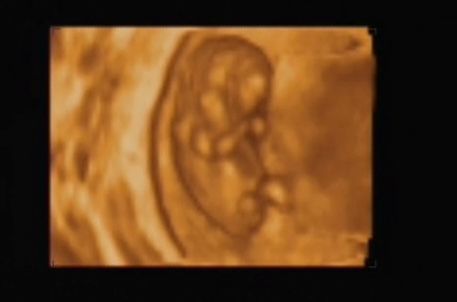

...Szerettem volna veletek megosztani, hogy hogy ficánkolt a drágám, de ilyen rossz hir után most képtelen vagyok!

A lényeg, hogy minden rendben van, és hogy uh szerint még nagyobb is egy héttel! Hallottam kalapálni a kis szivét, láttam a kezecskéit és a lábait...

A nyaki redőnk 0.7 vagyis tökéletes.

Január 23-án megyek a következő vérvételre az integrált teszt miatt!

Van dvd a kicsimről, csináltam nektek belőle képeket:

Kép Kép Kép Kép

Ági, köszönjük a képeket, nagyon jók lettek – szuper! Még a köldökzsinor is látszik :D és, még az is, ahogy a kezecskéit mozgatja.... jéééééé

Áááááááááági!!! Ez egyszerűen egy tökéletes bébike!!! És hogy már milyen nagy baba! Hihetetlen, hogy meg van mindene!!! Hol voltál 3D-s UH-n? Az integrált tesztet majd alkalomadtán meg fogom tőled kérdezni, mert most én is tervezek majd menni. Mindent meg akarok tenni a megnyugvásomért! Remélem, most már maximálisan nyugodt vagy a kis bébit illetően!

Amugy a Bolgárkerék utcában voltam integrált teszten. Ha jól tudom még Juci is ott volt. Isten igazából nem is a 3D-s volt a nagy része a vizsgálatnak, hanem, hogy a Down-kór szűrés. És az egészben az a jó, hogy pont az én dokibácsim van ott az uh-on! :) Mindent megmért, a combcsonttól kezdve a pulzust, az orrcsontot, a fejét... A 3D-sből ennyit csinált amit láttok. Majd késöbb elmegyek mégegyszer, amikor majd a szivét is jól látni, és akkor is csináltatok dvd-t.

Ez egyszerűen csodálatos volt! Úgy mozgolódott, sőt a látjátok a méhem milyen alakú... A drágám feljebb ugrált és onnan "csúszdázott le" (a doki ezt a szót használta). Csodálatos volt látni mindent. Sőt a doki még azt is megnézte, hogy mi van a lába között... Azt mondta csak tipp, és hogy ne vegyük készpénznek, de mintha lenne valami a lába között :D ...azért én még reménykedek,hogy kiscsaj, mert megnéztem a könyvben (csodálatos utazásban), hogy ilyenkor még a lányoknak is kitüremkedik, és nem lehet igazán megkülönböztetni! :roll: :lol:

És igen, kicsit megnyugodtam. Bár egy mondat megmaradt bennem és tudom, hogy azt fogom várni majd a következő uh-on: "gyomor és hólyag telítődése jelenleg nem ábrázolódik" De szerintem ehhez még kicsik is vagyunk... :(